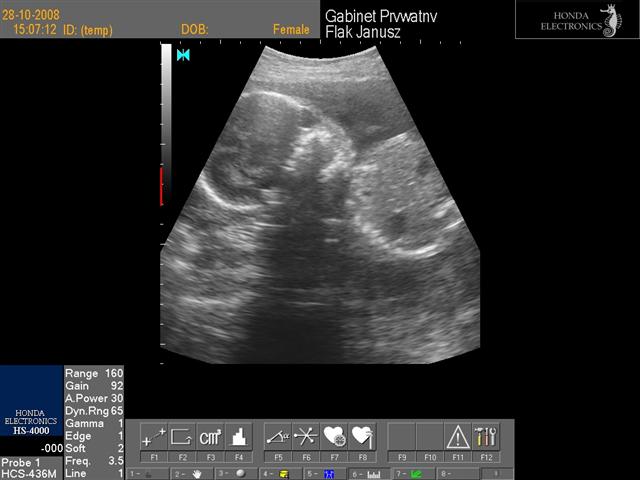

hej dziewczynki świerzo po wizycie wklejam fotki mojej córci(chyba dziewczynka....nie potwierdzone...ułożenie pośladkowe) to juz 24 tc+1 dzień